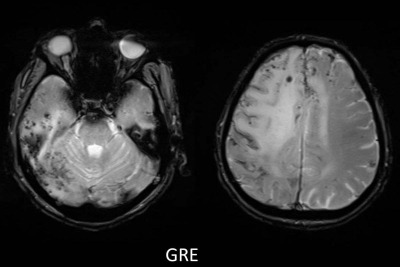

- C) Gradient seride milimetrik hemosiderin kalıntıları ve süperfisyal siderozis (kırmızı ok)